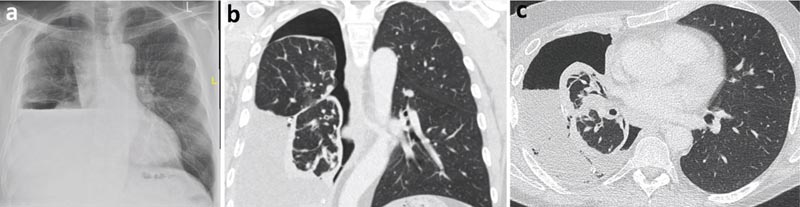

Une radiographie pulmonaire après thoracentèse thérapeutique a révélé la formation d’un hydropneumothorax, évoquant la possibilité d’un poumon non expansible. Une analyse liquidienne de l’épanchement pleural exsudatif a été demandée (protéines 40 g/l et LDH 620 UI).

La cytologie a révélé un épanchement lymphocytaire sans cellules malignes. La tomodensitométrie (TDM) du thorax a mis en évidence un cortex pleural pariétal englobant principalement le lobe inférieur droit, provoquant probablement un poumon non expansible.

Figure 2

a) Radiographie thoracique post-thoracentèse avec hydropneumothorax (air et liquide dans la cavité pleurale).

b) Scanner thoracique, vue coronale.

c) TDM thoracique, vue axiale.